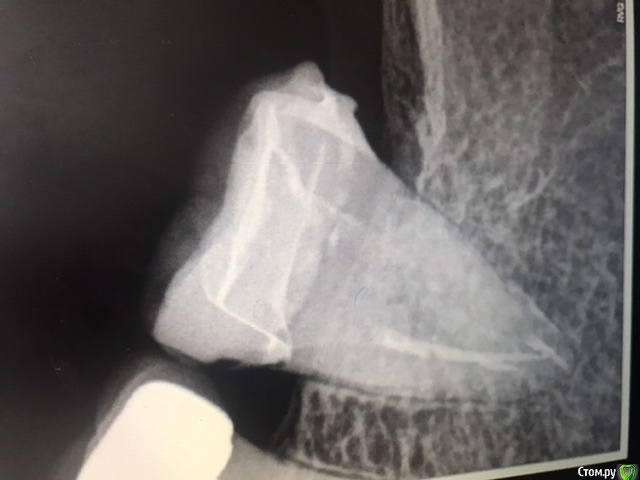

Уважаемые доктора. В 7-ой нижний зуб слева была установлена керамическая вкладка. Началось жжение языка, дискомфорт. Долго думали, решили высверлить вкладку. Ортопед изготовил новую керамическую вкладку, потом решили перелечить каналы, так как нашли дополнительный канал. Затем ортопед установил заготовленную ранее вкладку и зуб начал болеть. Жжение возобновилось и добавилось к боли. Доктор установил временную коронку, корректировал ее несколько раз, так как десна воспалена и в итоге сказал ,если беспокоит надо удалять. Пожалуйста выскажите своё мнение по моей ситуации. Добавляю снимки после перелечивания каналов, после установки вкладки, КТ до лечения. Благодарю за ответы.

post-11530-0-27528100-1600953928_thumb.jpeg